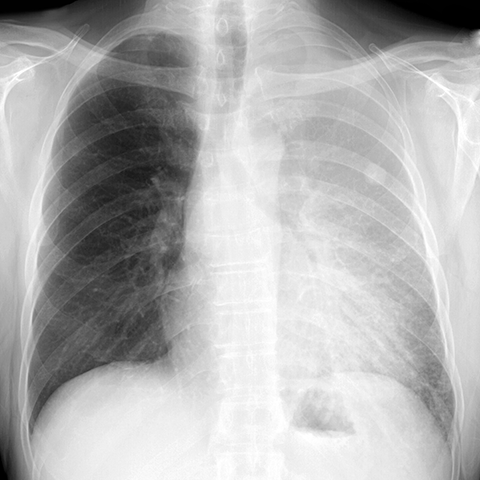

Left Upper Lobe Pneumonia [1 of 2]